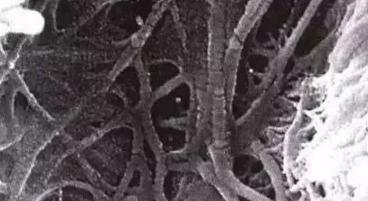

圖示樹脂突(放大倍數(shù)1500)